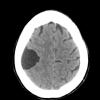

10A1 Cyst, arachnoid (Case 10) CT - Copy

10A2 Cyst, arachnoid (Case 10) FLAIR - Copy

10A3 Cyst, arachnoid (Case 10) T1noC - Copy

10A4 Cyst, arachnoid (Case 10) T2noC A - Copy